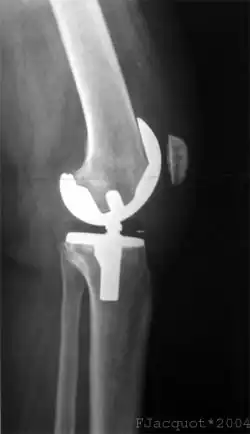

Röntgenaufnahmen leisten keinen unmittelbaren Beitrag zur Diagnosestellung einer Kreuzbandruptur. Beide Kreuzbänder sind – ob gerissen oder nicht – im Röntgenbild nicht sichtbar. Wird dennoch geröntgt, so kann dies der Diagnosestellung von möglichen knöchernen Begleitverletzungen dienen.